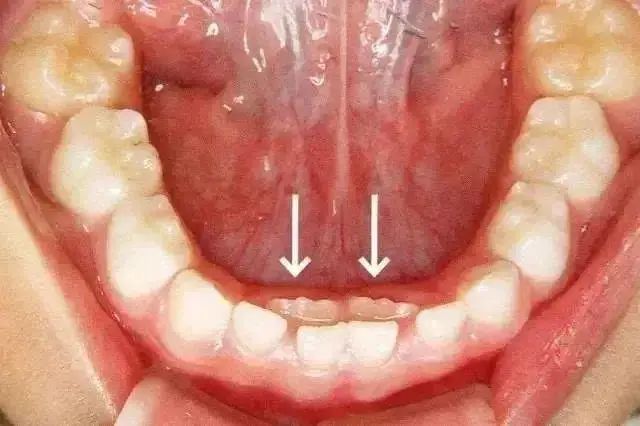

乳牙滞留是(shì)指恒牙相(xiàng)繼長(cháng)出,乳牙未能(nén•♦g)及時(shí)脫落。或者恒牙未萌出,保留在恒牙列中。π≠乳牙的(de)脫落與恒牙的(de)生(shēng)長(cháng)之∑λδ間(jiān)存在著(zhe)密切的(de)關系β∏。這(zhè)種情況多(duō)見(ji• "àn)于換牙期的(de)下(xià)颌門(mén)牙,恒牙長(cháng)在舌側,←'乳牙留于唇側,出現(xiàn)雙排牙。

三、雙排牙一(yī)定要(yào)拔嗎(ma)?

很(hěn)多(duō)家(jiā)長(cháng)看(kàn)到(d©$φào)孩子(zǐ)“雙排牙”後非常著(zhe)急,要(yào)求醫(yī)生(shēng)趕緊≠♠拔掉,這(zhè)樣對(duì)嗎(ma)?

過早過多(duō)的(de)拔牙,容易造成孩子(zǐ)牙颌畸形,拔不(bù)拔牙首先要(₹↔$yào)看(kàn)恒牙萌出的(de)高(gāo)度,當恒牙隻萌出 1/3 或者 2/3 ,且前排&✔ ₹牙齒還(hái)沒有(yǒu)松動的(dδ✘e)情況下(xià),建議(yì)家(jiā)長(cháng)先讓孩子(zǐ)多(duō)吃(ch§™ī)硬性食物(wù),比如(rú)啃蘋果、玉米等,促進自(zì)然脫落。

恒牙已經完全長(cháng)出來(lái),保留下(xià)來(l $♦πái)的(de)乳牙應該馬上(shàng)拔掉。将下(xià)颌的(de)乳牙拔掉後,長(chγ ±áng)在後面的(de)恒牙可(kě)以恢複正常的(de)排列。如(rú)果牙齒>Ωσ排列不(bù)當,應選擇恰當時(shí)間(jiān)矯正!乳牙拔除過程中可(kě)能(n←∑ éng)出現(xiàn)根斷裂,由于殘根較接近(©≤jìn)恒牙,可(kě)以不(bù)治療,牙根會(huì)被自(z±✔αì)身(shēn)吸收或随著(zhe)恒牙的(de)爆發脫落。